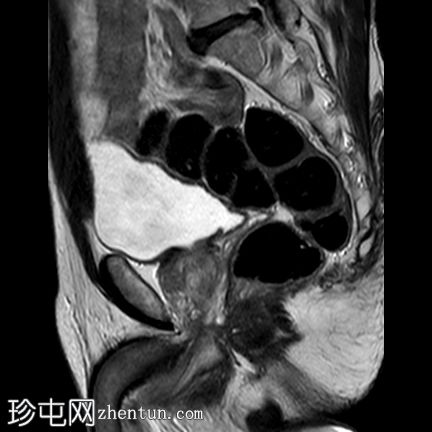

轴位

ADC

前列腺体积40 ml。PSA 9.6 ng/ml。PSA密度0.24 ng/ml/cc。

右侧前列腺前中带可见一边界不清的18 x 10 mm扁豆状病灶,T2加权像呈低信号,扩散受限(DWI高信号,ADC低信号),与周围实质相比早期强化,病灶位于前移行区与纤维肌性间质交界处。影像学表现符合PI-RADS 5级病灶。

一例经活检证实为低级别前列腺癌(Gleason评分3+3=6)的患者,目前正接受积极监测。